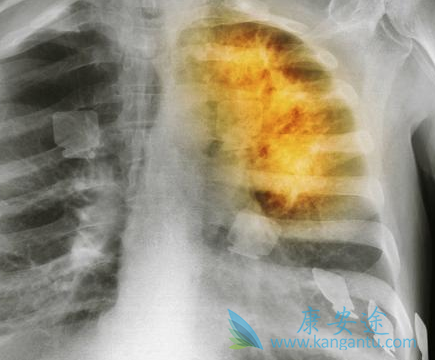

一般来说肺癌患者只要被确诊为晚期,患者和家属就会很迫切的想知道,治疗情况如何?晚期有救吗?虽然说癌症目前还不能达到完全治愈的目的,但仍有不少晚期肺癌患者带瘤生存,治疗效果不错,生活质量也很高的案例。肿瘤不止手术切除、放化疗、中医治疗等方法,由于病由心生,患者首先需要在心理上克服癌症。那么肺癌晚期还有救吗?下面一起来看看。

上面这三种情况是肺癌患者常常碰到的问题,因此不论患者是否已经做过手术,或者正在进行放化疗治疗,或者已经结束了治疗,正在家中依靠中药继续巩固治疗,若能及时进行热疗、排毒、三氧等绿色综合治疗,其生存期能得到延长。对于仍有肿瘤存在的患者,绿色综合治疗可大大提高肺癌晚期患者生存质量,抑制肿瘤恶变,这也是患者“带瘤生存”最明显的表现。在祈福医院肿瘤科,超过5年生存期的带瘤患者比比皆是。一位阿姨患病时已62岁了,至今6年过去了,生存现状非常好,生活自如,经常到户外锻炼,也如其他健康老人一样,经常旅游,还有些肺癌老人还能自驾到处去玩,生活质量非常高。